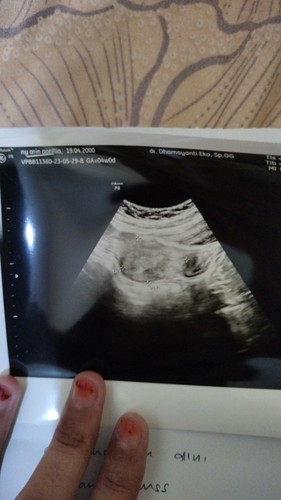

Mau tanya kemarin USG apakah itu sudah bisa di sebut hamil ? Karena hasil tespacnknya udah garis 2

Hasil USG

Kalo udah ada kantong kehamilan nya berarti ya hamil bun, itu kan udah ada keterangan usia nya GA 4w0d berarti baru 4minggu, nanti usg ulang lagi sekitar 2-3minggu lagi biasanya udah kelihatan janin dan ddj nya Banyak2 istirahat dan konsumsi vitamin bun karena diusia kandungan yang sekarang masih rentan keguguran